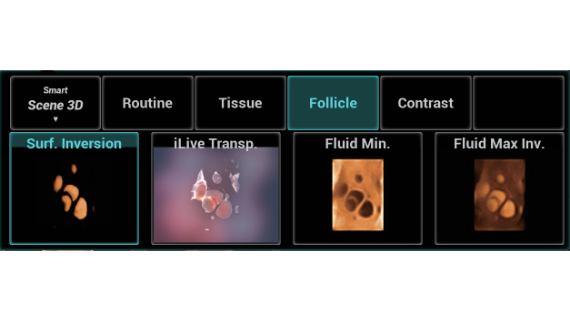

El sistema Nuewa I9, dise?ado exclusivamente para la atenciĂłn mĂ©dica neonatal y de mujeres, brinda una experiencia innovadora integral. Estas innovaciones se desarrollan sobre la base de un conocimiento profundo de situaciones clĂnicas complejas para proporcionar respuestas precisas y oportunas, una gran eficiencia y una experiencia de usuario extraordinaria.

La plataforma ZST+?es una innovaciĂłn extraordinaria que representa toda una evoluciĂłn en el ĂĄmbito de la ecografĂa. Transforma las mĂ©tricas ecogrĂĄficas de la formaciĂłn de haces convencional al procesamiento basado en datos de canal. Supera la limitaciĂłn tradicional de tener que equilibrar entre resoluciĂłn espacial, resoluciĂłn temporal y uniformidad del tejido, con lo que ofrece una calidad de imagen excepcional para soluciones de producciĂłn de imĂĄgenes infinitas con mejoras continuas.